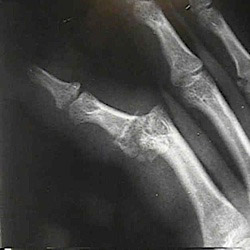

Description Of The Injury: A proximal interphalangeal (PIP) joint dislocation is the dislocation of the joint that is just proximal to the knuckle. The PIP joint area contains a strong ligament called the volar plate and collateral ligaments around it. Dislocation of this area usually occurs when the finger has been hyper extended in some abrupt way. This causes the ligament to tear from its attachment.

Injury Symptoms: The most critical sign is pain and swelling at the proximal interphalangeal joint. Flexing the finger at the middle phalange will be difficult and will result in considerable pain. Occasionally the area may also be deformed as a minor piece of bone may have been pulled away due to the impact.